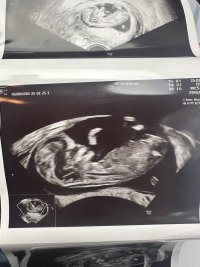

Sniker litt12+0 og alt så fint ut (enn så lenge). Veldig mye aktivitet, så var ikke lett å måle hjertefrekvensen «mye overskudd», sa jordmor

vil bare informere om at fullt navn og personnummer viser på bilde Vis vedlegget 456171

Lov å tippe kjønn om dere vil/ser noe![]()

JenteVis vedlegget 456171

Dette er tydelig ei jente!Vis vedlegget 456171

Synes det ser ut som en liten gutt13+2 og alt bra

Tror ikke det er mulig å se nub her?

Tipper jente!Vis vedlegget 456171